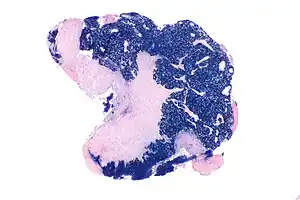

Micrograph showing a nasopharyngeal carcinoma positive for Epstein-Barr virus-encoded small RNAs (EBER).

Type 3 is most commonly found among younger children and adolescents, with a few type 2 cases. Both type 2 and 3 have been found to be associated with elevated levels of Epstein-Barr virus titers, but not type 1. Additionally, type 2 and type 3 may be followed with an influx of inflammatory cells, including lymphocytes, plasma cells, and eosinophils, generating the term lymphoepithelioma.[15]

Nasopharyngeal carcinoma, also known as nasopharyngeal cancer, is classified as a malignant neoplasm, or cancer, arising from the mucosal epithelium of the nasopharynx, most often within the lateral nasopharyngeal recess or fossa of Rosenmüller (a recess behind the entrance of the eustachian tube opening). The World Health Organization classifies nasopharyngeal carcinoma in three types, in order of frequency: Non-keratinizing squamous cell carcinoma; keratinizing squamous cell carcinoma; and basaloid squamous cell carcinoma.[16] The tumor must show evidence of squamous differentiation, with the non-keratinizing type (also known as lymphoepithelioma) the tumor most strongly associated with Epstein-Barr virus infection of the cancerous cells.[17]